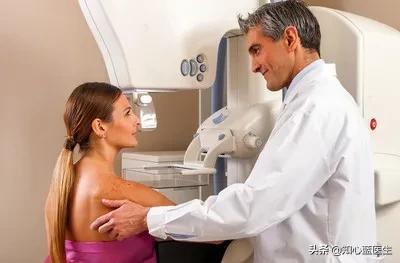

5、超音波検査とマンモグラムに対する乳がんの恐怖。

40歳未満の女性には超音波検査を、40歳以上の女性にはモリブデンを推奨する。

一般的な40歳未満の女性ができる自己検診は、乳房そのものにしこりやはみ出し、見た目の変化などがないか観察し、問題が見つかった場合は速やかに医師の診察を受けることである。

マンモグラフィは、40歳以上の女性には1年に1回、数年続けて問題がなければ2年に1回が推奨されている。

乳腺が密集している、つまり乳腺が多い乳房の場合は、マンモグラフィをお願いします。

6.乳がん

乳腺は表在性の臓器であり、女性は自分で乳腺を触って、特に結節があるかどうかを確認することができます。ほとんどの人は乳房超音波検査で十分ですが、危険因子の高い人はマンモグラフィ検査を受けるべきです。マンモグラフィは超音波検査よりも正確ですが、放射性物質が含まれるため、すべての人に推奨されるわけではなく、超音波検査で問題が見つかった場合は、再度マンモグラフィを受けることを検討した方がよいでしょう。

乳がん検診乳房超音波検査は、乳房のしこりの有無を明らかにすることができます。一般的に、超音波検査はマンモグラフィ(モリブデンターゲット)と併用して乳がんのスクリーニングに使用されます。 乳房結節にがんが疑われる場合、大きさ、範囲、リンパ節転移をさらに明確にするために強化MRIが必要となり、最終的には性状をはっきりさせるために性状穿刺生検が必要となります。

(1) 乳がん

20歳から39歳までの女性。年1回を推奨触診。

40歳以上の女性は年1回が推奨される触診+マンモグラフィ。

がんの家族歴や乳がんの既往歴など、危険因子の高い女性には、検診の頻度を増やすことが推奨される。

腫瘍マーカー:CEA(癌胚抗原)、CA-125、CA-153。

(5)40歳以上の女性、高度の小葉異型過形成の女性、小葉がん in situの女性は、年に1回乳がん検診を受けることが推奨される。

検診の焦点:乳がん

経験:X線マンモグラフィ、MRI、超音波検査

X線マンモグラフィはより正確ですが、あまり頻繁に行うべきではありません。